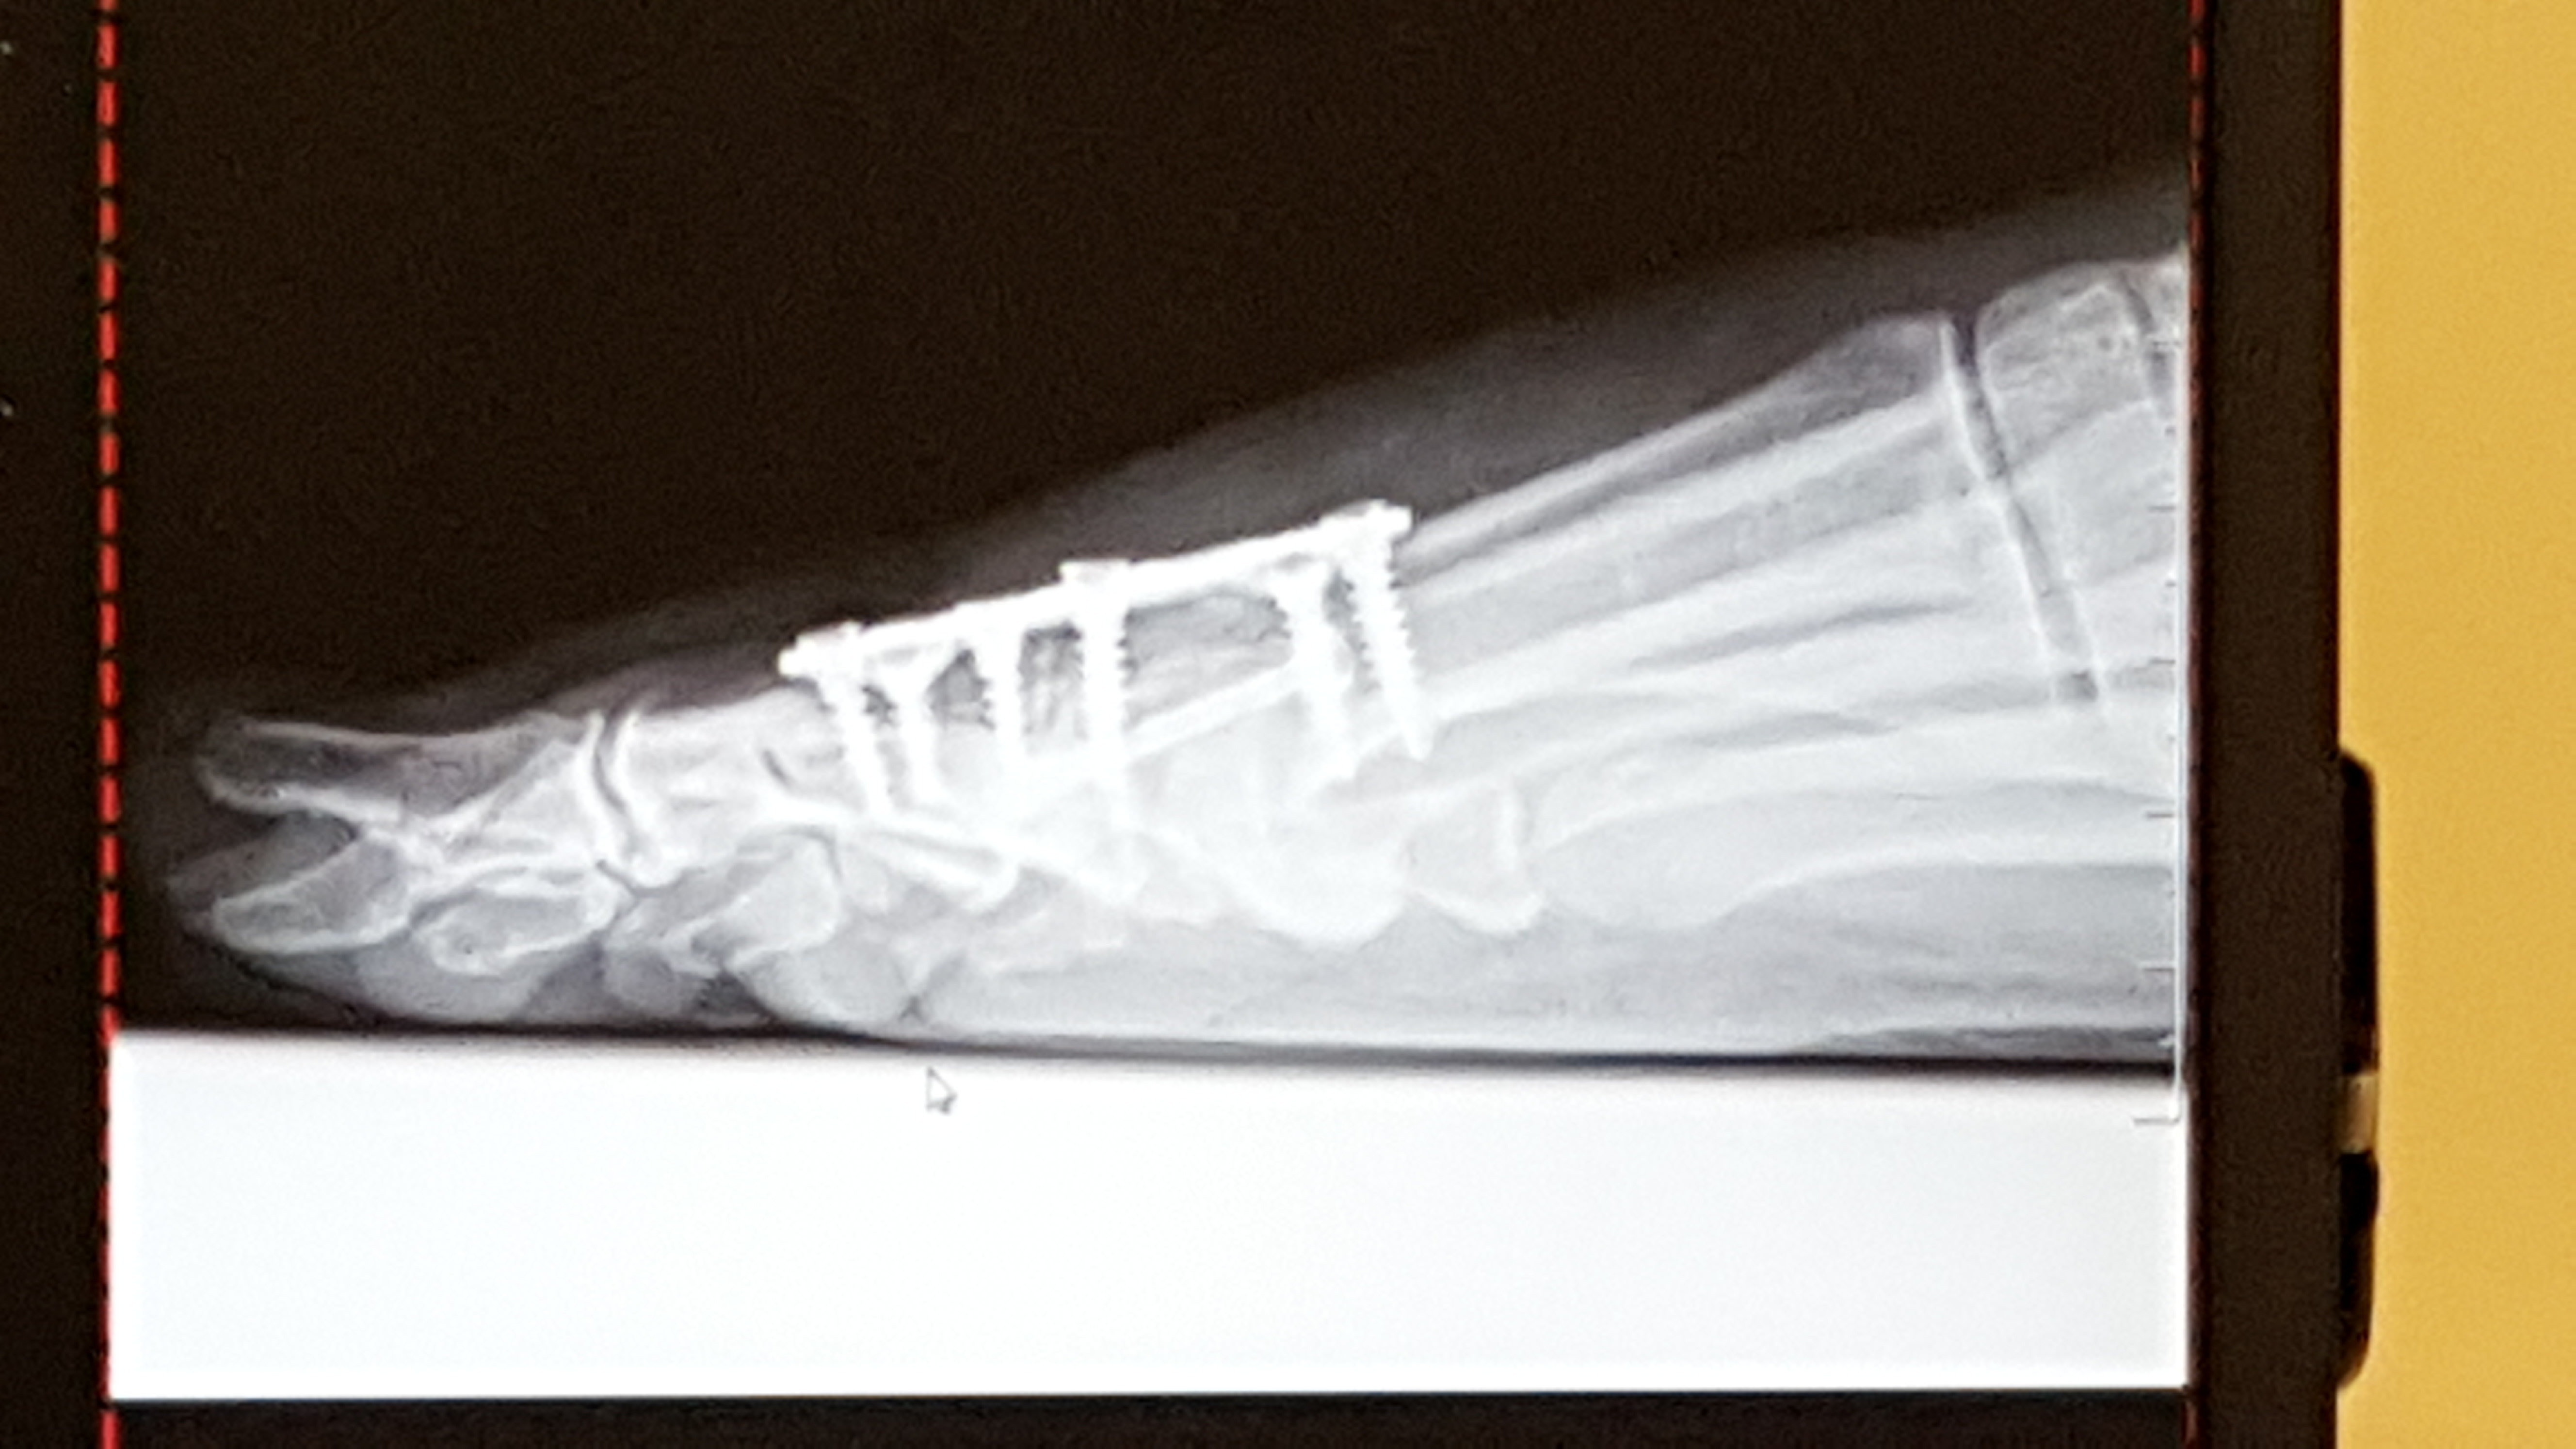

foot side October 4, 2018 ~ msgracefulnot Published by msgracefulnot So hard when someone says tell me about yourself...what do you want to know? View all posts by msgracefulnot